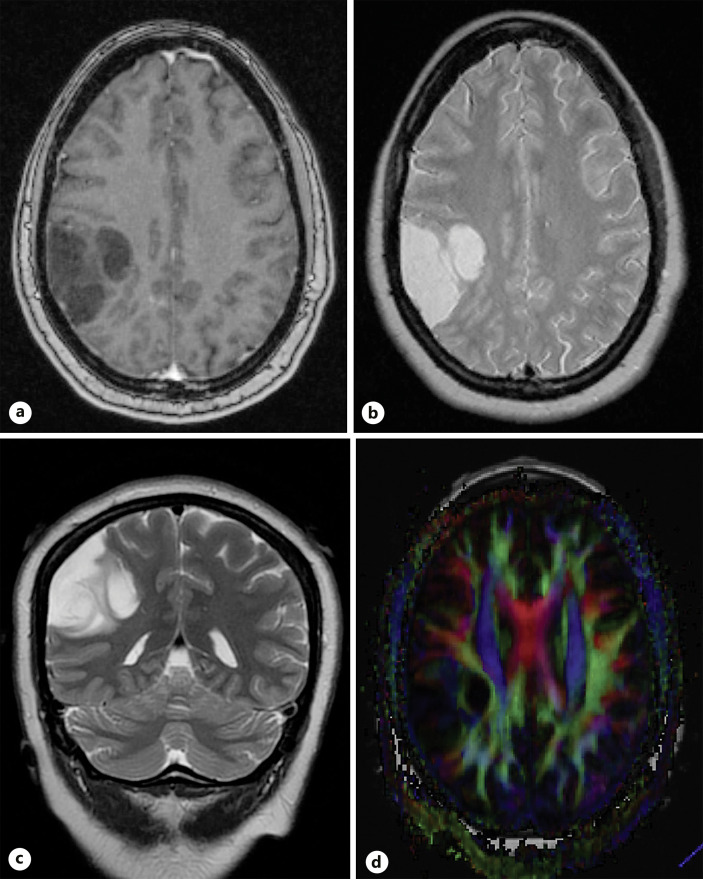

Case presentation: The current article describes the case of a 40-year-old G3P1101 female at 10 weeks' gestation, who sought medical care for recurrent left hemifacial twitching, eventually leading to nonconvulsive status epilepticus. Intubation and sedation were required to achieve seizure cessation. Imaging revealed a lobulated cystic mass in the right parietal lobe, suspicious for low-grade glioma. Despite thorough explanation of the potential risks, the patient adamantly wished to pursue surgical intervention. An uneventful craniotomy was performed for resection of a low-grade glioma. No patient or fetal complications were encountered, and the patient has not had any reported seizures since surgery.